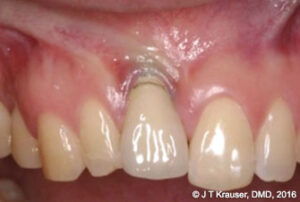

This article focuses on an alarming issue of implants loosing support and integration due to excessive soft tissue pull or tension from a shallow vestibule and/or dense frenum pull. We now have an abundant number of cases that exhibit tissue recession and possibly late loss failure. For example, Figures 1A-1C show a case of late implant failure. In 1996, the patient received

an implant on tooth No. 8. The immediate result was very good, both functionally and aesthetically (Figure 1A). However, the 2007 follow-up visit revealed severe gingival recession (Figure 1B depicts the recession and distinct frenum pulls). The cross-sectional image from 2007 (Figure 1C) demonstrates the lack of bone in the facial and apical aspects of the implant. The presence of frenum pulls (evident in Figure 1A from 1996) should have been a reason for concern. We believe that a prophylactic release of the frenum pull prior to implant loading would have prevented such outcome. Today, we would have addressed the frenum pull with a CO2 frenectomy prior to implant loading.